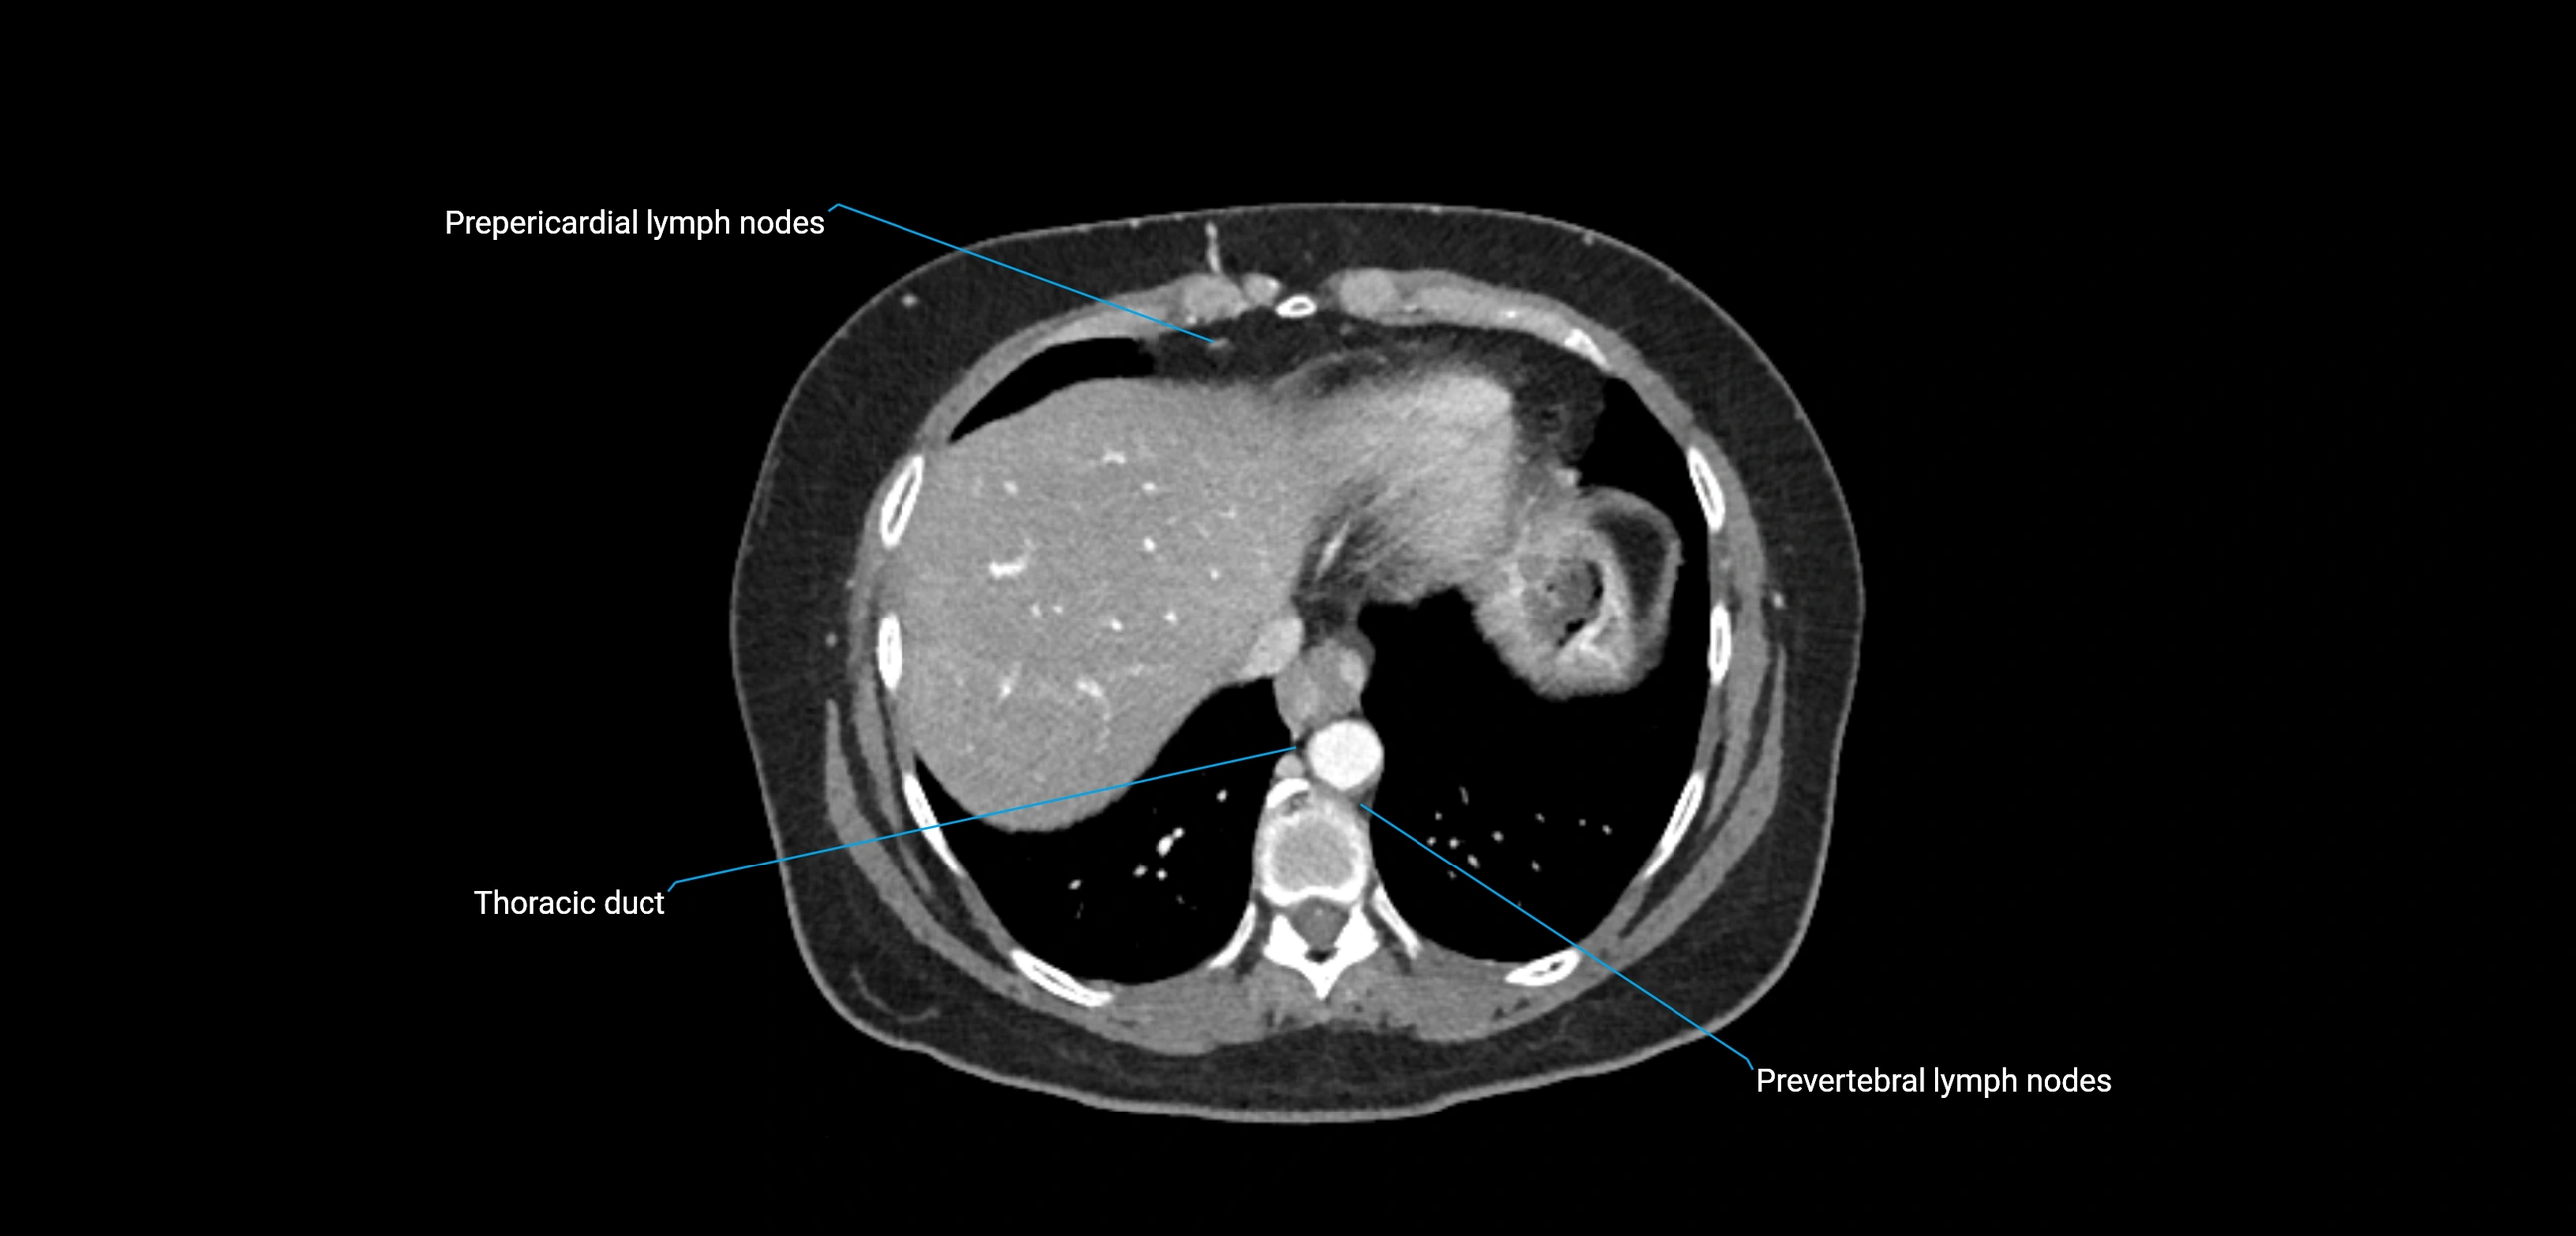

CT Appearance

CT Pre-Contrast:

• Nodes appear as soft-tissue density nodules adjacent to the aorta and IVC

• Calcification may be seen in chronic infections (e.g., tuberculosis)

CT Post-Contrast:

• Normal nodes enhance homogeneously

• Malignant nodes may show heterogeneous enhancement, central necrosis, or conglomerate formation

• Size >1 cm short axis is suspicious, though morphology and distribution are equally important

CT image

image